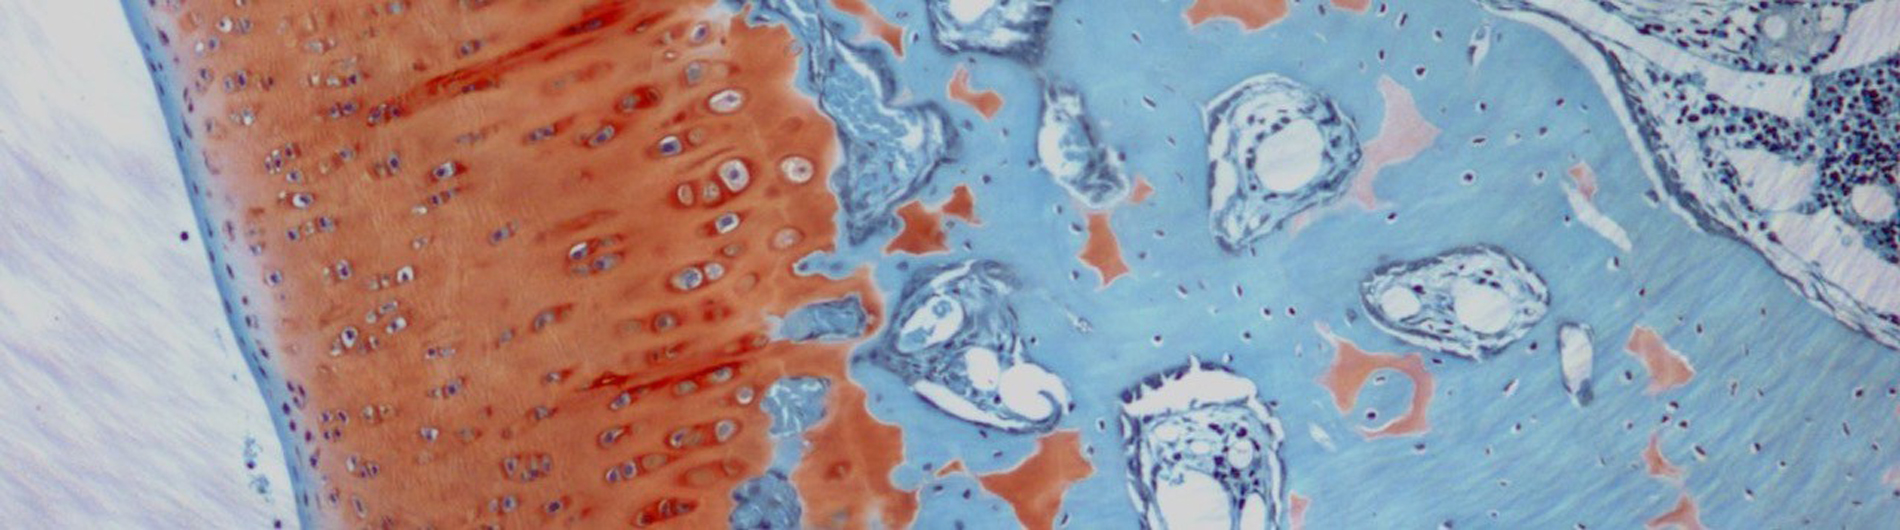

Finite element model of the knee meniscus.

The emphasis in our laboratory is on the use of computational modeling to study biomechanics in personalized treatment planning. Our interests include studying the role of gender, obesity, ethnicity, activities and meniscal injuries in the development of knee osteoarthritis. Using models based on medical imaging techniques such as micro-computed tomography and magnetic resonance imaging, our goal is to better understand the distribution of forces in the knee joint and how these may be related to risks for the onset or progression of osteoarthritis. In similar studies, we also are investigating the cornea and methods to identify individual material characteristics that may influence treatment options. We use statistical methods to expand experimental studies from their use as validation to also allow for robust predictions of anticipated performance.